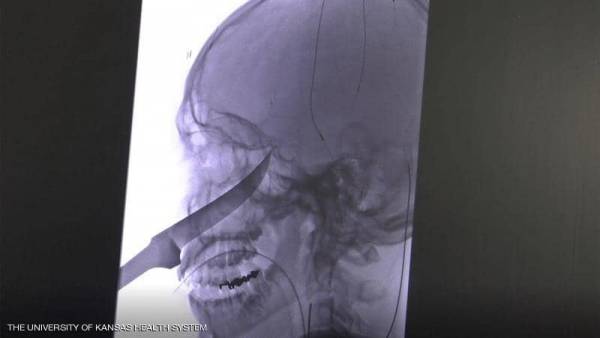

أخبار البلد - نجح فريق طبي أميركي في إنقاذ حياة مراهق من ولاية كانساس، تم نقله إلى المستشفى بينما كان سكين طوله 25 سنتيمترا يخرج من جمجمته.

وأضافت جيمي، التي لا تزال على غير علم بكيفية إصابة ابنها: "في البداية اعتقدت أن الصراخ طبيعي، ثم جاء إيلي إلى الباب وعندما فتحه كان وجهه عبارة عن كتلة من الدم وقطعة معدنية تخرج منه، كان الأمر صادما للغاية".

وتابعت: "اعتقدت أنه قضيب معدني، وبعد ذلك استطعت أن أرى أنه يشبه مقبض سكين وهذا ما كان عليه فعلا، وفكرت مباشرة بالاتصال بالشرطة".

وفي مستشفى ميرسي للأطفال في كانساس، هرع المسعفون حيث رأى الأطباء احتمال تلف الشريان السباتي في دماغه، الأمر الذي كان سيؤدي إلى الإصابة بالسكتة الدماغية أو أضرار جسيمة، فقرر الأطباء نقله إلى نظام الصحة بجامعة كانساس.

وهناك تم تخصيص فريق طبي تمكن في أقل 24 ساعة من إنقاذ إيلي، الذي يخضع حاليا للعلاج بمجموعة من المضادات الحيوية واللقاح ضد الكزاز (التيتانوس)، فيما أمره الأطباء بالابتعاد عن أي أشياء حادة.